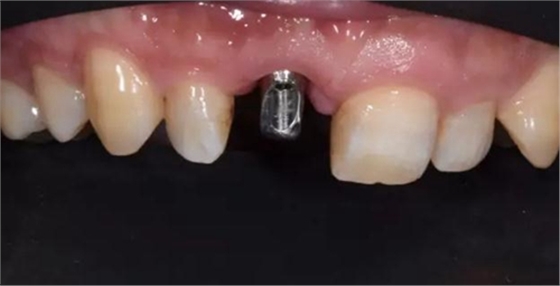

評估C先生身體狀況和口腔內(nèi)情況后。選擇了種植修復。

種植體植入后